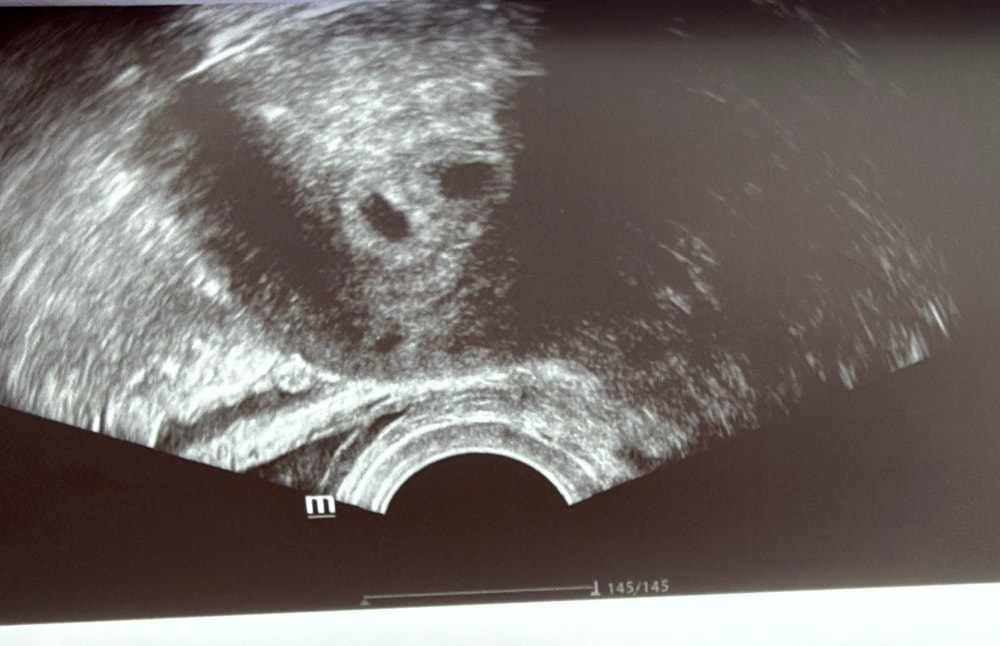

Результаты УЗИСходила на Узи для подтверждения маточной беременности

Плодное яйцо -6 мм, по-моему маленькое..

ЖМ пока нет , это нормально или нет? (

Я вижу 2 😱